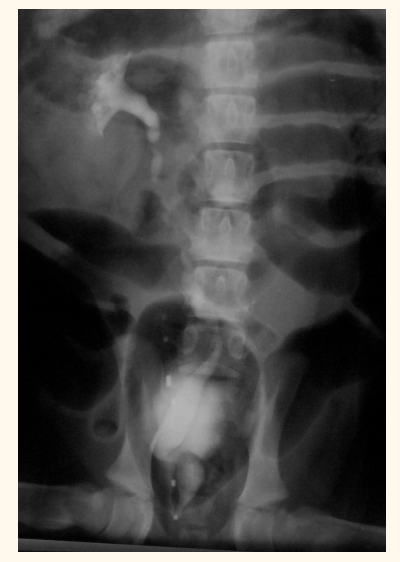

contrast radiography. what does this px have

air -ve contrast

whats wrong with this patient

ectopic ureter— hydroureter